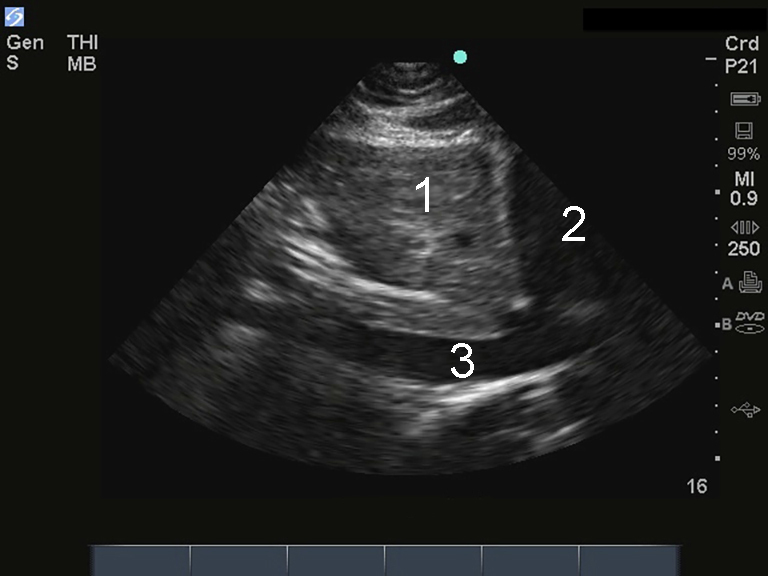

M-Turbo:IJV 長軸画像

M-Turbo:IJV 長軸

肝臓

心臓

IVC